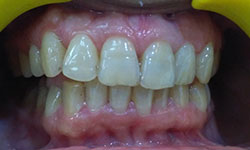

(10) Dental Implant - Full Mouth

Before Treatment

After Treatment

Patient came with a problem in chewing food and multiple loose teeth in upper and lower jaw and was interested in getting a whole new set of teeth in both the jaws. So after removal of all the weakened teeth and placement of multiple implants, he was given implant supported bridge.